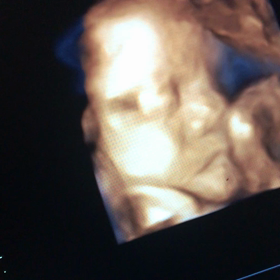

• 33w1dの画像

33w1d